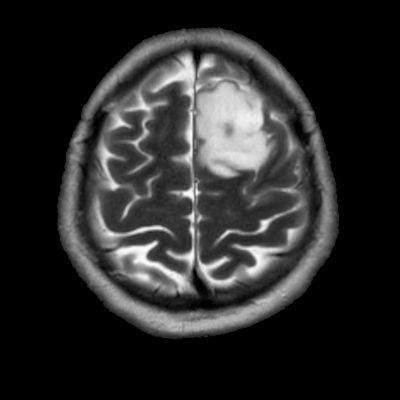

- Sol frontal kortikal-subkortikal yerleşimli aksiyel T2A görüntüde hiperintens sinyal özelliği gösteren (oklar) ve FLAIR görüntüde sinyali ağırlıklı olarak baskılanan (oklar) kitlesel lezyon izleniyor. Lezyon T1A görüntüde hipointens olup post-kontrast T1A görüntüde bu düzeyde patolojik kontrastlanma izlenmiyor (oklar).

- FLAIR’de T2’ye benzer şekilde hiperintens görünür. Ancak T2–FLAIR mismatch bulgusu, bu tümör tipi için oldukça karakteristiktir.

- T2–FLAIR mismatch bulgusu, T2AG’de homojen hiperintensite ile FLAIR görüntüde santral sinyal baskılanmasının ve çevrede hiperintens halka görünümünün bulunduğu bir fenomendir. Bu bulgu, özellikle IDH-mutant, 1p/19q kodelesyonu olmayan astrositomları tanımlamada oldukça özgül bir biomarker olarak literatürde vurgulanmıştır. Ayırıcı tanıda akla gelmesi gereken oligodendrogliomlarda T2/FLAIR mismatch bulgusu genellikle görülmez.

- Olgumuzda T2-FLAIR mismatch bulgusu mevcut olup, opere edilmiş ve tanısı histopatolojik olarak konulmuştur.